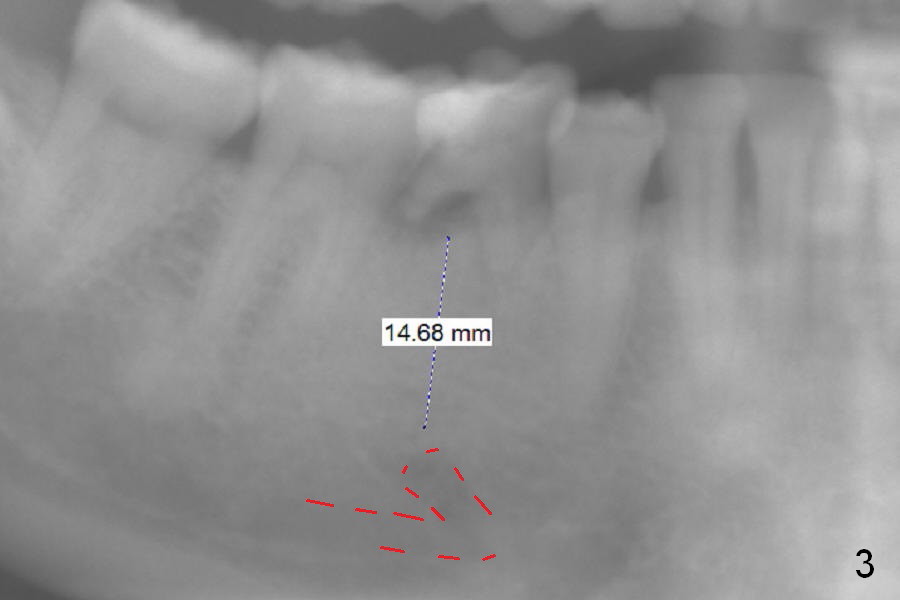

Wide Ridge of Retained Primary Molar

A 39-year-old woman has periodic mobility and pain of the lower right 2nd primary molar. It appears that the mesiodistal width of the tooth has decreased in the last 7 years (Fig.1,2). After extraction and Clindamycin/10 drops of 1:1000 Epinephrine gauze for 3 times, use LR plastic quadrant tray and PVS to take impression of the socket for education purpose. Try using Magic Expanders, but Magic Drills will be most likely used to finalize the osteotomy, since the bone density does not seem to be low. The initial depth will be 11 mm for IBS implant (Fig.3).